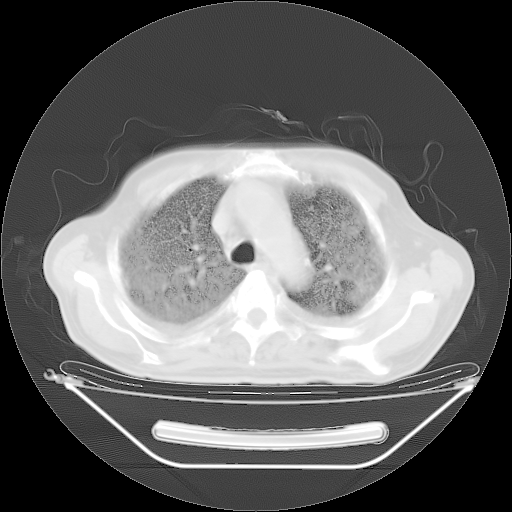

今天复查肺部CT,发现双肺广泛磨玻璃样改变。所以我把3月19日和5月9日相隔50天的肺部CT上传。请大家会诊。

5月9日肺部CT(在4月27日齐鲁医院肺部CT描述部分肺组织磨玻璃样改变,12天后肺组织广泛磨玻璃样改变)

2009年5月9日肺部CT

大致读了系列胸部CT:纵隔窗无明显异常,肺窗:从4、27至今:主要是双肺中下野外带可见毛玻璃样改变,目前处于急性肺泡炎阶段,至于原因考虑1、结替组织或胶原血管性疾病所致?2、恶性疾病如恶组在肺部所致的表现或细支气管肺泡癌?3、药物或其它原因如肺蛋白沉着症所致肺泡炎目前不太可能?总之,明天就去请我院的呼吸科、感染科、血液科和临免专家会诊哈。